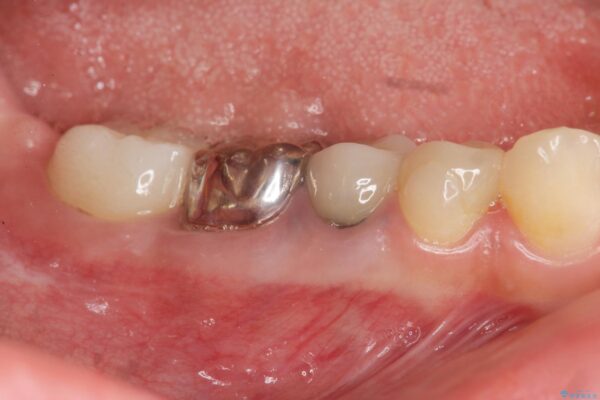

X線写真検査より、クラウンや銀歯の下で歯に大きな虫歯が発生し、抜歯を余儀なくされる状況でした。

虫歯に伴い歯槽骨の吸収も見られたので造骨後、インプラントを用いて咬合機能を回復します。